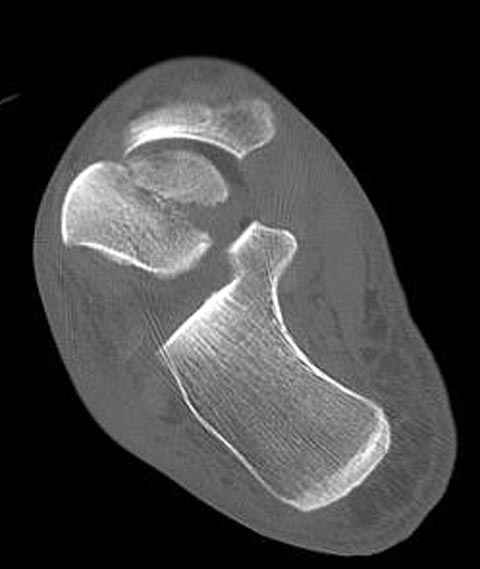

Уважаемые участники русского Ортофорума, поздравляю всех со всеми прошедшими праздниками: Новым годом, Рождеством, Hanukkah, Kwanzaa, желаю участникам всего наилучшего и здоровья.Повреждение таранной кости.Больной 81г автоавария, повреждение таранной кости, здесь снимки. Какие рекомендации?Djoldas Kuldjanov, MDDepartment of Orthopedic SurgerySt. Louis University Medical Center

Вдогонку по поводу перелома таранной кости, больная 81, не страдает диабетом, перелом закрытый, в первый же день поступления ограничились временным наружным фиксатором (как на снимке).

Из-за отека на стопе тактика лечения у всех была

одинаковая: временная наружная фиксация до спадения отека, при изолированных переломах они выписывались домой и через дней 7 госпитализировались на оперативное лечение.

Примеры на снимке...